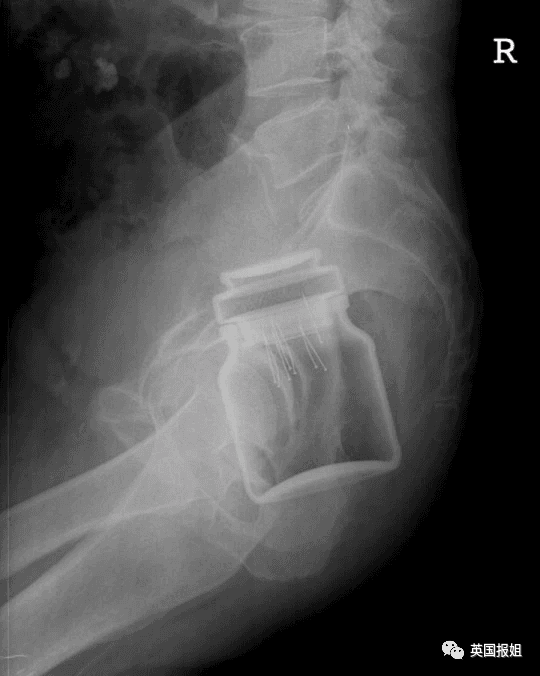

左:茄子 右上:铝罐 右下:咖啡罐

可以看出这些患者对于球形的、柱状的和长条形的物体有一些奇怪的执念。但有些患者也会突破这些形状的桎梏,寻找更多样的物品嵌入体内。